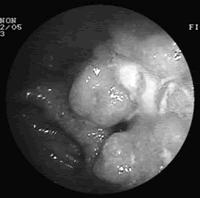

德国学者采用双气囊小肠镜(DBE)对小肠病变进行复杂的介入治疗,包括氩离子凝固术(APC)、息肉切除、球囊扩张术和支架置入等,安全性较好。[Am J Gastroenterol 2007,102(3)∶527]

该研究纳入从2003年6月到2006年6月在德国Mainz大学教学医院就诊的353例患者,其中女性152例,男性201例,平均(60.3±17.1)岁。纳入患者均疑似或确诊为小肠疾病,共进行了635例次的DBE检查。

DBE对小肠病变的总诊断率为75%,其中210例(60%)为小肠出血 ......